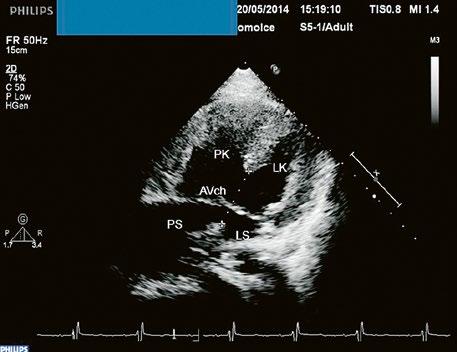

Obr. 45.14 TTE, čtyřdutinová apikální projekce. Kompletní atrioventrikulární septální defekt je označen křížky, představuje komunikaci mezi oběma síněmi i komorami se společnou atrioventrikulární chlopní (AVch)

LK – levá komora, LS – levá síň, PK – pravá komora, PS – pravá síň